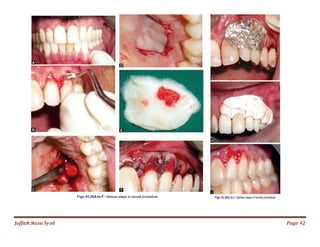

Jаffaя яaza Syзd Page 42